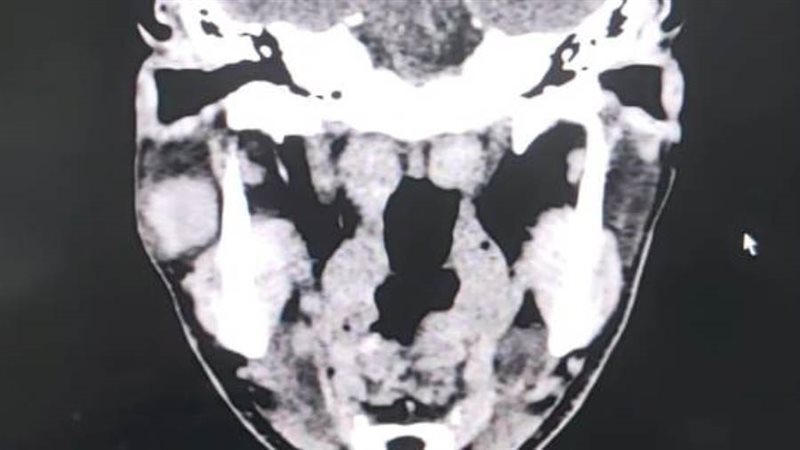

قام قسم جراحة الوجه والفكين بمستشفى ادكو المركزى فى إجراء عملية دقيقة لإزالة ورم من الغدة النكافية "ورم حميد بالغدة النكافيه من الفص السفلي لها" وبفضل الله تم الحفاظ على العصب الوجهي السابع.